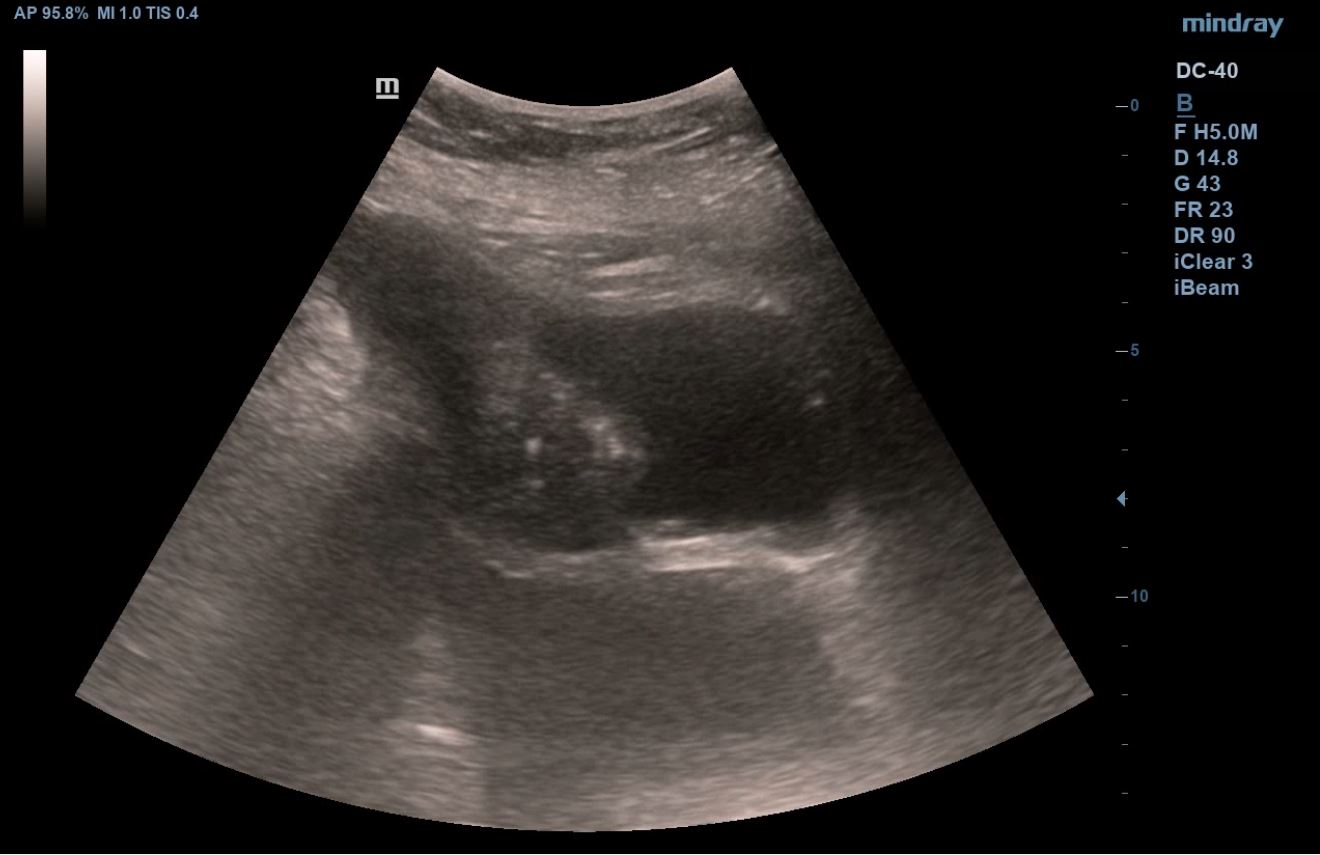

Se realiza ecografía clínica abdominal y pulmonar en la consulta, donde se visualiza líquido libre en espacio hepatorenal, esplenorenal y espacio de Douglas. En región pélvica presenta masa de aspecto heterogéneo con zonas anecoicas de 12 x 10 cm, con mapa color positivo. En la ecografía pulmonar presenta derrame pleural derecho.